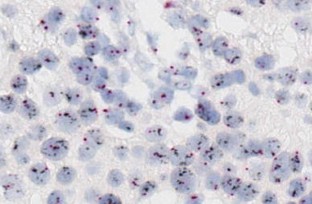

Molecular-targeted therapy using trastuzumab, a humanized monoclonal antibody against human epidermal growth factor receptor type-2 (HER-2), is considered to be effective for metastatic as well as primary breast cancer and has already become a worldwide standard therapy for patients with HER-2 protein over-expression and gene amplification. Pretreatment evaluation of HER-2 status is considered to be essential for selection of patients, and according to the generally used algorithm, cases with an immunohistochemistry (IHC) score of 3+ and positivity upon fluorescence in situ hybridization (FISH) are thought to be eligible for trastuzumab therapy. In order to develop an appropriate domestic HER-2 testing system in Japan, the Trastuzumab Pathology Committee was established in 2000 and has been used as a forum for active discussions of policies related to HER-2 testing. After trastuzumab therapy and HER-2 testing had become widely adopted internationally, new guidelines for HER-2 testing were proposed by the ASCO/CAP group in 2007. Since then, these guidelines have gradually become accepted and used in many large-scale clinical studies of HER-2-targeting agents. On the other hand, new ISH methods have been introduced, such as bright-field HER-2 and chromosome 17 centromere double in situ hybridization (BDISH) and dual color-chromogenic in situ hybridization (dc-CISH). These methods make it possible to examine HER-2 gene amplification using only one paraffin section like the dc-FISH method, and to observe grains on the HER-2 gene and centrosome-17 by conventional microscopy. These approaches are considered to be reliable and equally as effective as the dc-FISH method. Accurate evaluation of HER-2 status is thought to be most important for appropriate selection of breast cancer patients who will obtain genuine benefit from trastuzumab treatment. In order to perform effective evaluation of HER-2 status, it is necessary to establish a reliable HER-2 examination system and to maintain its quality at a high level.

Fig. 1

Fig. 2

Fig. 3

Fig. 4